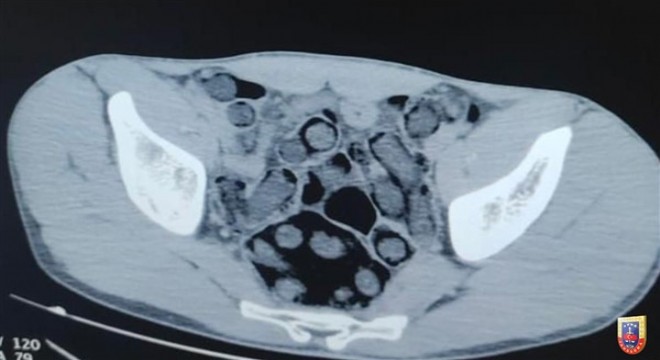

Mide ve bağırsaklarında eroin taşıyan 2 kişi yakalandı

Jandarmanın operasyonunda mide ve bağırsaklarında eroin taşıyan 2 kişi gözaltına alındı.

Jandarma Genel Komautanlığından yapılan açıklamada, ''Bitlis İl Jandarma Komutanlığınca yapılan istihbari çalışmalar neticesinde gerçekleştirilen operasyonda, mide ve bağırsaklarında 176 kapsül halinde 1 kilo 96 gram eroin maddesi taşıdığı tespit edilen 2 şüpheli yakalanmış, şüpheliler sevk edildikleri mahkeme tarafından tutuklanmıştır.'' denildi.